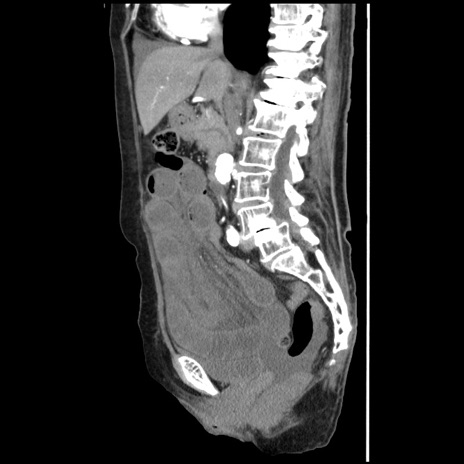

症例1(矢状断像)

【症例】80歳代女性

【主訴】腹痛

【現病歴】8時間前から腹痛あり来院。

【既往歴】糖尿病、脂質異常症、子宮体癌にて子宮全摘術

【身体所見】意識清明・会話良好だが腹痛で苦悶様、全腹部にわたって反跳痛と圧痛あり

【データ】WBC 13600、CRP 0.14、LDH 224、CK 90